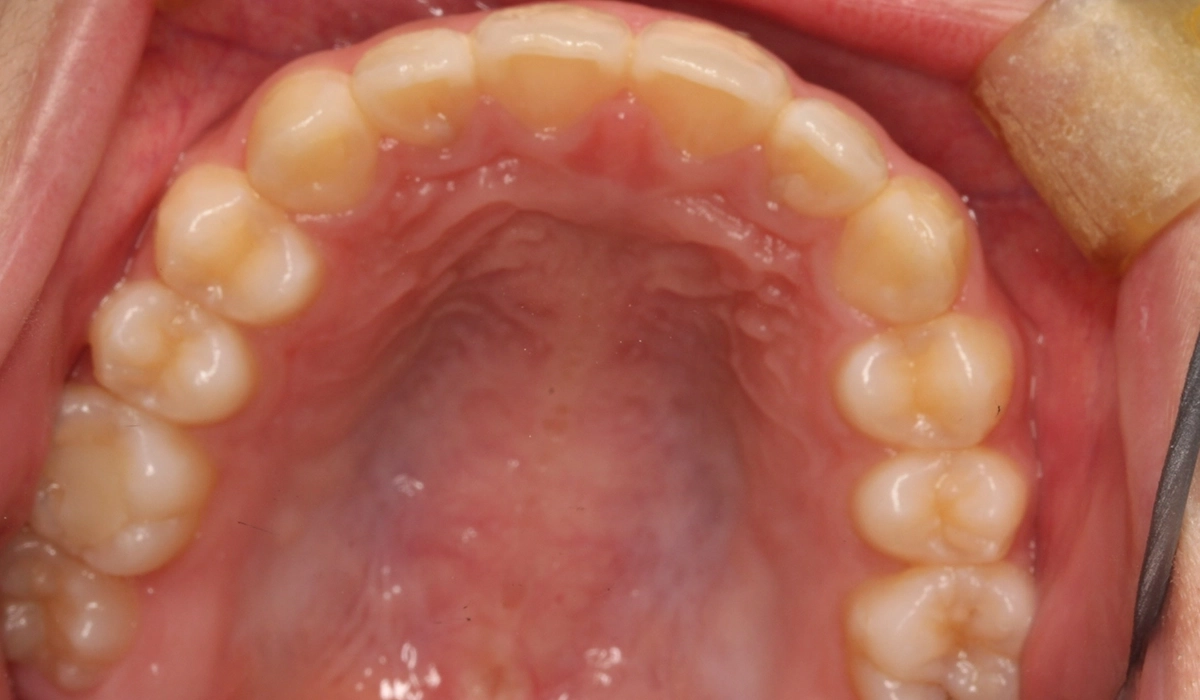

術前:下顎

術後:下顎